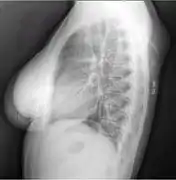

X-ray of a lipoma

X-ray showing lipoma